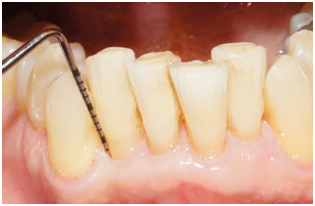

Supportive periodontal therapy was performed on a regular basis starting 6 weeks after surgery and every three months making sure not to instrument the surgical site subgingivally. The patient’s plaque control was optimal. The patient was recalled 6 months after surgery. Full mouth periodontal charting was completed. The disto-facial surface of tooth #26 exhibited a remarkable reduction in PD and BOP (Table 2). The patient was pleased with the esthetics and function. 12 months follow up was performed that revealed stable periodontal readings when they were compared with the 6 months readings. At the 12 month reevaluation, the PD was 3mm at the disto-facial surface of #26. There was a CAL gain of 6 mm (Figure 9) (Figure 10). Table 2 present clinical measurements at baseline, 6 and 12 months and documents a tendency for continued improvement in PD and CAL from baseline.

Figure 9 Probing 12 months after surgery reveals PD of 3 mm on the disto-facial aspect of tooth #26.